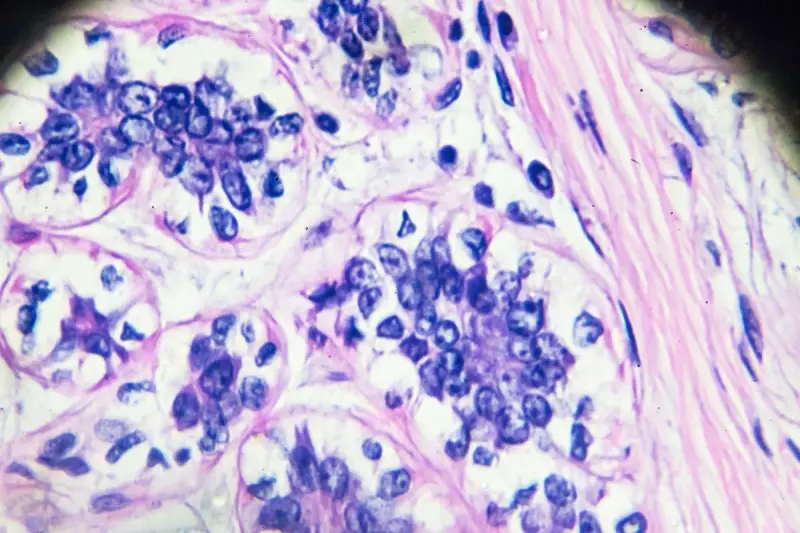

A concerning new study has revealed that many women are mistaking early signs of breast cancer for symptoms of COVID-19 or flu, leading to dangerous delays in diagnosis and treatment.

Researchers found that common breast cancer symptoms such as fatigue, weight loss, and persistent pain are being dismissed as viral infections. This misdiagnosis trend has emerged particularly since the pandemic began, with many patients avoiding medical visits due to fear of COVID-19 exposure.

Early detection is crucial for successful breast cancer treatment. When diagnosis is delayed, cancer can progress to more advanced stages, significantly reducing survival rates. The study emphasises that while some symptoms overlap with viral infections, their persistence should trigger medical investigation.